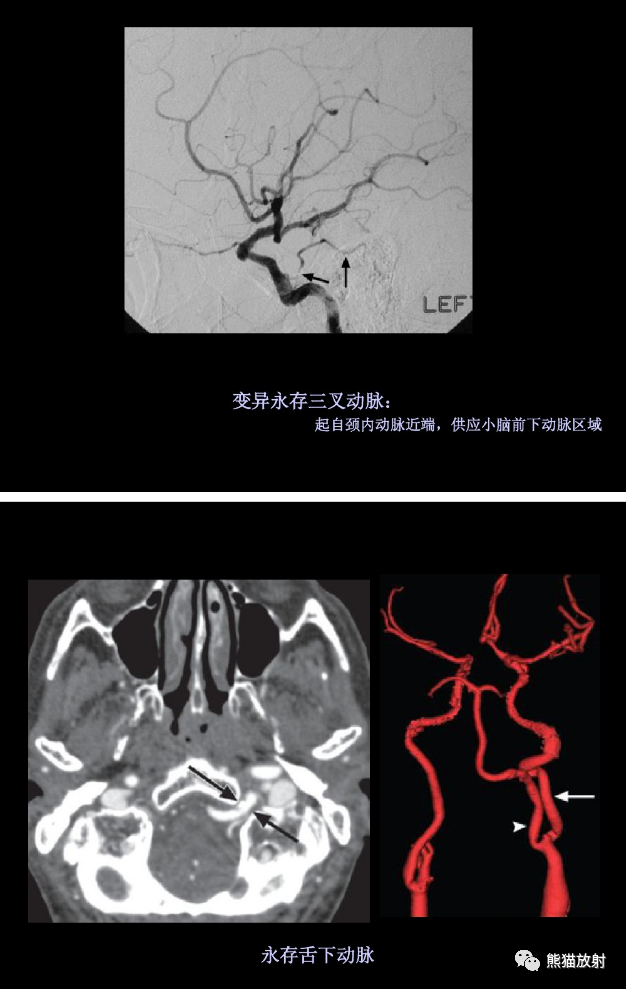

大脑前动脉 ACA,大脑中动脉 MCA,大脑后动脉 PCA,前交通动脉 ACoA,后交通动脉 PCoA,颈内动脉 ICA